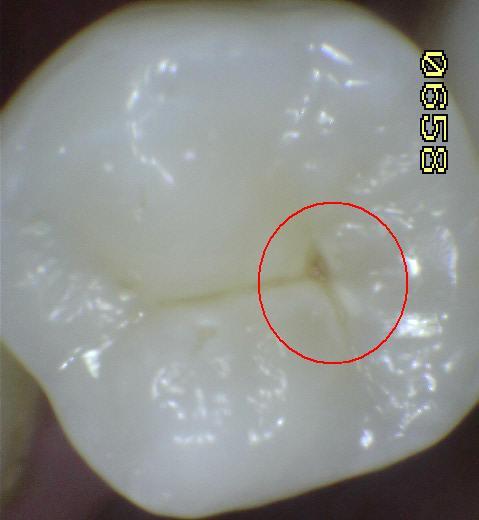

2. CÓDIGO 3

1. Ruptura localizada del esmalte, En húmedo se observan lesiones opacas o decoloradas. En seco se observa pérdida de estructura dental sin dentina visible. (Microcavidad)

1. DIAGNOSTICO DENTAL: CARIES CAVITACIONAL (ACTIVA / NO ACTIVA). Es activa cuando a la exploración clínica con cucharilla el tejido cariado se puede retirar acompañada de otros signos como encía enrojecida y presencia de sangrado, cuando es inactiva vemos que hay dentina reparativa de por medio, esta se ve opaca y no brillante.

1. TRATAMIENTO: Orientación en normas y educación de higiene oral al padre/madre/menor, control de placa, profilaxis, sellante o restauración de mínima invasiva y aplicación de barniz fluorado.